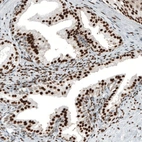

Immunohistochemistry analysis in human fallopian tube and cerebral cortex tissues using AMAb91547 antibody. Corresponding AR RNA-seq data are presented for the same tissues.